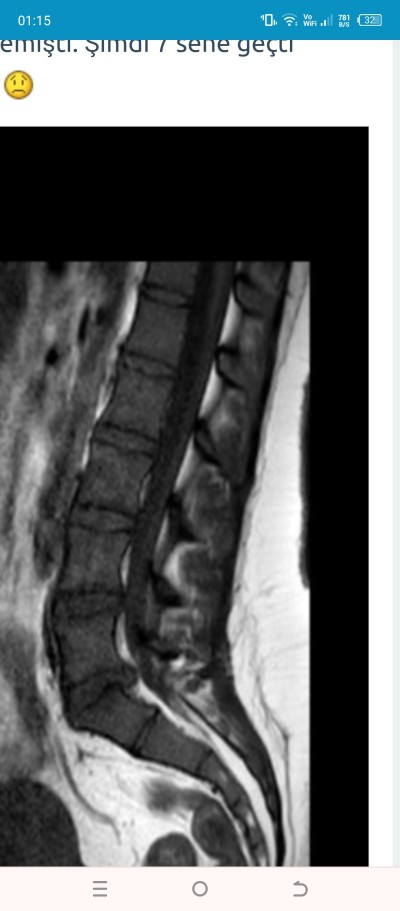

En son 7 sene önce Mr çekilmiştim. Şikayetlerim iyice arttı diye kontrole gittim bugün mr çekildi ama sonuçları gosteremiyorum hemen. Daha önce yaşayan, anlayan var mı acaba. Daha 27 yaşındayım. İlk 19 yaşında belim tutulup Mr çekilince fıtık demişlerdi. O zaman doktor yaşın genç olmasaydı ameliyat derdim ilerlemiş fitiklarin ama yaşın genç demişti. Şimdi 7 sene geçti korkuyorum :(

image